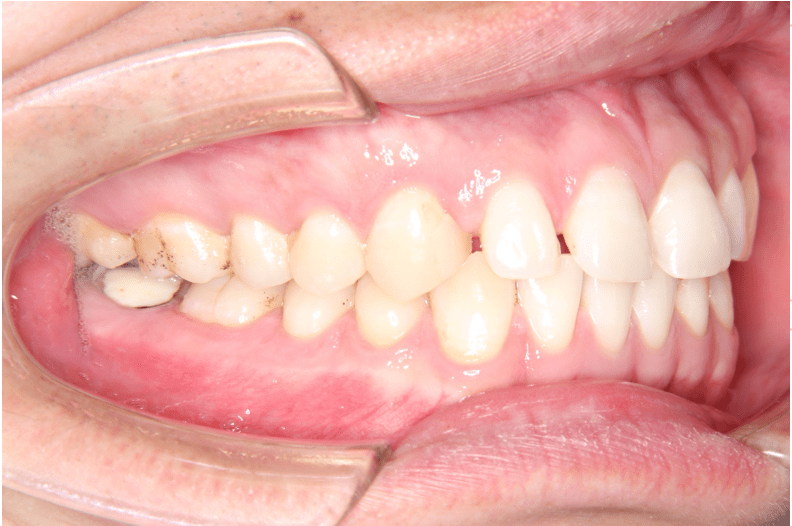

治療前(左)

歯列に隙間が見られます